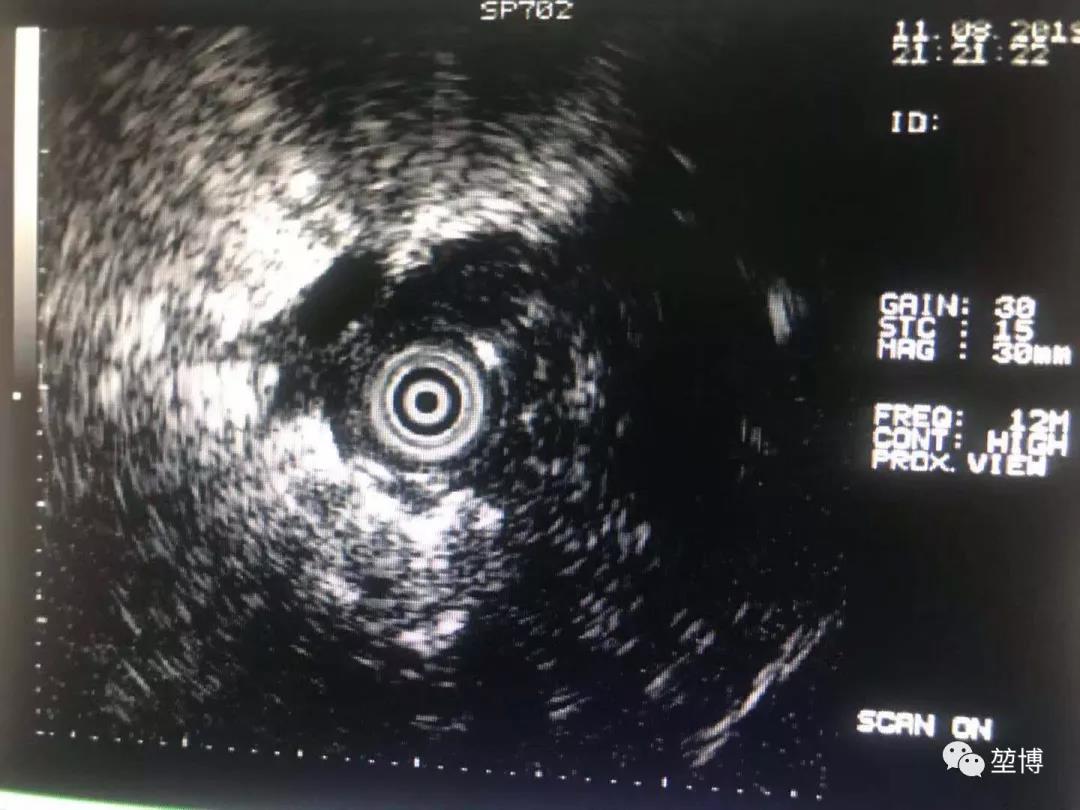

在LungPro引导下抵达RB3开口处,按照术前规划的避开血管的POE穿刺点进行穿刺,X光透视下鞘管顺利抵达病灶中央,经肺实质建立隧道,再将激光光纤送入,行激光消融术。

超声确认抵达病灶